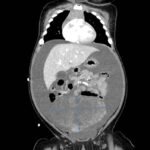

A 5-month-old female presented to the emergency department with worsening abdominal distention and postprandial emesis. Point-of-care ultrasound (POCUS) demonstrated extensive abdominal free fluid with a large, heterogeneous mass in the suprapubic region. This was confirmed on computed tomography (CT) of the abdomen and pelvis. The patient was urgently taken to the operating room for exploratory laparotomy where a ruptured tumor was discovered. The patient was eventually diagnosed with ovarian juvenile granulosa cell tumor. POCUS can be vital in guiding the recognition of rare pediatric conditions in the emergency department and should be considered in patients where there is concern for an acute abdomen.